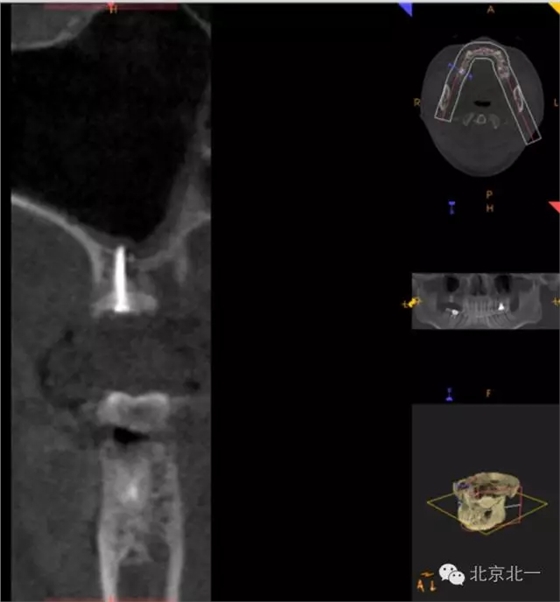

圖十六:植入植體

圖十七:縫合。非潛入

圖十九:手術后當天CBCT

圖二十-二十二:ONLAY植骨半年后

圖二十三:種植后當天全景片。